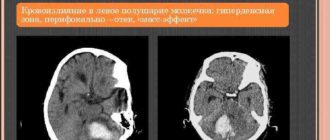

Микрокровоизлияния в левой гемисфере мозжечка

Венозная ангиома правой гемисферы мозжечка головного мозга: что такое, симптомы, причины возникновения, лечение Ангиома